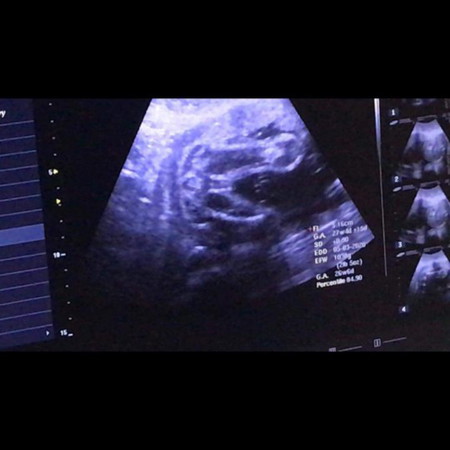

It's a girl. -kase if it's boy, parang walang lawit . Ito po yung sa baby ko, parang same position and view sila. Hehe

Its a girl! Its called the hamburger sign! 3guhit.

Girl. Walang lawit ehhh . 1😂😂😂